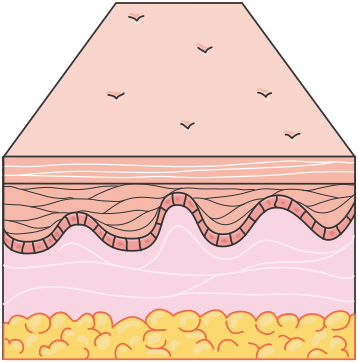

First-Degree Burns: These are superficial burns affecting only the epidermis. They present with erythema, mild swelling, and pain. First-degree burns typically heal within 3 to 7 days without scarring. An example of a first-degree burn is a mild sunburn.

Figure 1.21, generated using Servier Medical Art, provided by Servier, licensed under a Creative Commons Attribution 4.0 unported license